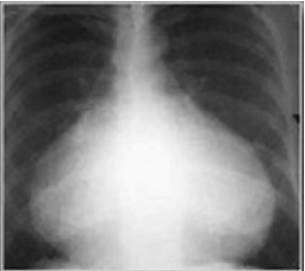

Uma adolescente de 12 anos foi levada à Emergência e sua mãe relata falta de apetite, mal-estar, náuseas e dor no peito, com irradiação para ombro esquerdo há 24 horas. A anamnese revela que foi submetida à correção cirúrgica comunicação intra-atrial (CIA) há 20 dias. O exame físico apresentou estado geral regular, t.ax: 382C; FR: 52 irpm; FC:100 bpm; PA: 100 x 60 mmHg; ACV: presença de discreto som de atrito pericárdico; AR: sem alterações; fígado e baço não palpados. Os exames laboratoriais apresentaram o seguinte resultado: HM: 4.800.00 mm³; Hb: 12,5 g/dL; Hto: 37,5%; Leucócitos 10.100/ mm³; B: 3%; S: 32%; L: 48%; VHS: 10 mm; RX de tórax. De acordo com o exposto, analise a imagem a seguir.